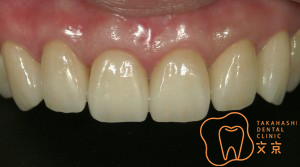

■前歯を治したい。 オールセラミックスによる審美治療

■前歯を治したい。40代男性 オールセラミックスによる審美治療

■前歯を治したい 精密審美治療・セラミックス治療

■前歯 精密審美治療

■前歯のセラミックス治療 審美治療

■前歯のオールセラミックス治療

■保険の前歯を直したい